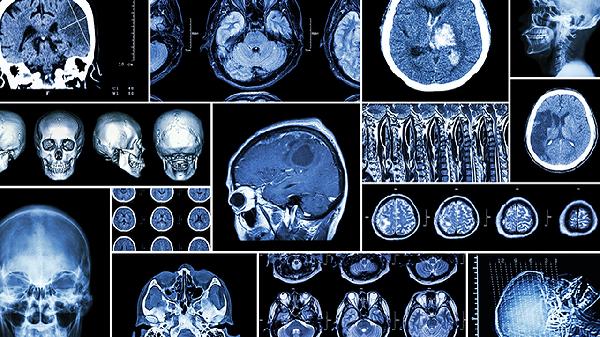

脑动脉硬化、早期阿尔茨海默病等器质性疾病可能表现为认知功能下降。这类情况常伴随定向障碍、性格改变等特征性症状,需通过脑部CT、神经心理学评估等检查明确诊断,及时进行药物干预和认知训练。